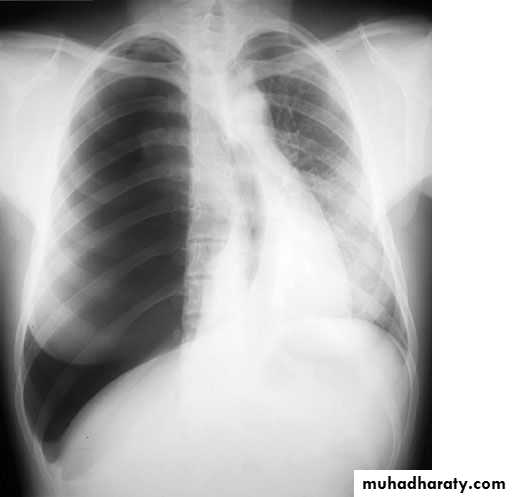

Radiopaque hemi-thoraxPneumothorax (air in pleural space )

Signs

Loss of vascular markings at the outer parts of lung fieldsDemarcating pleural line between the lung & vessels lacking area.

Well demarcating of the scapula

Epsilateral lung collapse

Tension pneumothorax

Emergency condition

Pressure effect on the mediastinum & major vessels

Treatment by chest tubes